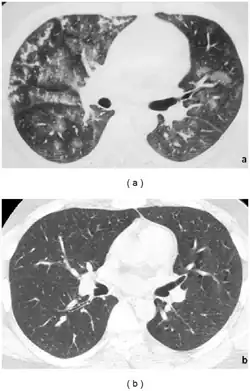

Clinically, IPH manifests as a triad of haemoptysis, diffuse parenchymal infiltrates on chest radiographs, and iron deficiency anaemia. It is diagnosed at an average age of 4.5 plus or minus 3.5 years,[6] and it is twice as common in females.[6] The clinical course of IPH is exceedingly variable, and most of the patients continue to have episodes of pulmonary haemorrhage despite therapy. Death may occur suddenly from acute pulmonary haemorrhage or after progressive pulmonary insufficiency resulting in chronic respiratory failure.